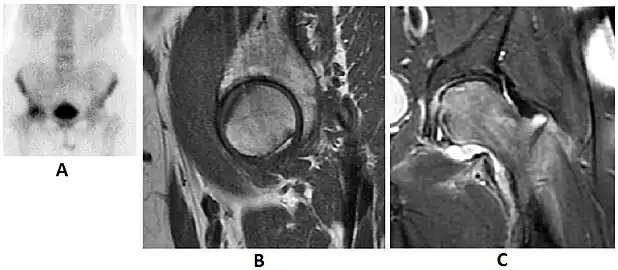

Radiological signs of transient osteoporosis of the hip include localized osteoporosis of the femoral head and neck (Figure 8). Nevertheless, final diagnosis has to be made with MRI to differentiate it from avascular necrosis and from insufficiency or stress fractures of the femoral head or neck. In case of AVN, radiographs can only demonstrate delayed or advanced signs. Staging according to Ficat classification ranges between normal appearance (stage I), slight increased density in the femoral head (stage II), subchondral collapse of the femoral head with or without “crescent” sign (stage III), and advanced collapse with secondary osteoarthritis (stage IV). In the case of stress or insufficiency fractures X-ray sensitivity has been proven to be much lower than MRI, which is currently the gold standard.[1]

Figure 8:

X-ray of a patient with transient osteoporosis of the left hip showing osteoporosis.[1]

Coronal stir imaging in transient osteoporosis, showing diffuse edema.[1]

Scintigraphy (A), sagittal T1 (B), and coronal PD fat sat of a patient with a subchondral fracture of the femoral head with convex shape to the articular surface.[1]

Coronal T1 of a patient with avascular necrosis of the femoral head.[1]